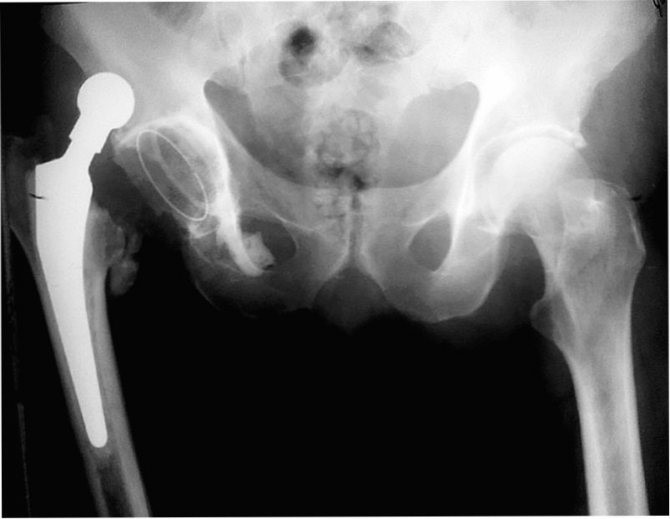

Вивих ендопротезу кульшового суглоба – це порушення контакту головки стегна з ацетабулярним (вертлужним) компонентом, що вимагає спеціальних заходів щодо вправлення та відновлення конгруентності поверхонь

Вивих ендопротезу можна запідозрити в першу чергу по різкій появі сильного болю в кульшовому відділі та/або в області паху. Вона вперто тримається навіть у спокої, посилюється за будь-якої спроби руху в суглобі. Схожого характеру симптоматика буває і при інших ускладненнях: при нестабільності протезу, тендиніті чотириголового м’яза, ізольованому відриві сідничного м’яза, бурсіті великого вертела та ін. Тому підтвердити справжню етіологію болю можливо тільки після клінічного огляду і виконаної рентгенографії.

Діагностика вивиху головки ендопротезу кульшового суглоба

Для підтвердження діагнозу та виключення переломів у ділянці ендопротезу призначають рентгенологічне обстеження.